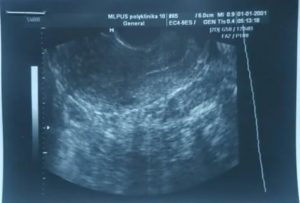

- УЗИ при беременности на ранних сроках важно и по причине возникновения внематочной беременности, которую можно и не увидеть. Связаны, такие проблемы, с особенностью прикрепления плодного яйца в аномальных местах и его маленькими размерами. Как раз поэтому, при ранних ультразвуковых исследованиях, предпочтение отдается трансвагинальному методу, ведь он на ранних сроках в разы точнее.

- Старые УЗИ аппараты, гораздо менее чувствительны, а значит, беременность они смогут диагностировать гораздо позже, на 6 неделе и выше.

- Что касается человеческого фактора, то тут все немного сложнее. Неопытный специалист или тот, кто ранее не имел дела с акушерством и гинекологией, может спутать плодное яйцо с опухолью и наоборот. Поэтому стоит тщательно выбирать место проведения УЗИ и уточнять информацию о специалисте, который будет проводить диагностику. Из-за этого, конечно же, не стоит полностью доверять первым ультразвуковым исследованиям, так как они бывают ошибочны. Нередко не удается определить беременность в связи с воспалительными процессами, ведь воспаление приводит к отеку, за которым плодного яйца попросту может быть не видно.

- Трансвагинальная диагностика выполняется путем введения датчика во влагалище. Такой вид УЗИ чаще всего применяется на более ранних сроках беременности и гарантирует более высокую точность результатов. Подготовка к трансвагинальному УЗИ не требуется, единственное — это необходимость опустошить мочевой пузырь перед исследованием и выполнить туалет наружных половых органов как при гинекологическом осмотре. Для проведения потребуется специальный презерватив, но необходимо приобретать его самостоятельно или нет — оповестит врач, который назначает или проводит исследование. В норме процедура безболезненна и занимает не более 10-30 минут.

- Трансабдоминальное проводится через переднюю брюшную стенку и рекомендовано на более поздних сроках, когда у плода уже появилось сердцебиение, где-то с 5-6 недели. На ранних сроках подготовка будет необходима. Она заключается в исключении употребления газообразующих продуктов за сутки до исследования, а затем, перед самим исследованием, потребуется наполнить мочевой пузырь. Это делается для улучшения прохождения ультразвуковых волн. На более высоких сроках, подготовка не нужна, так как плод достаточно велик и имеются околоплодные воды, которые являются хорошим проводником.

До 5 недель сформированное плодное яйцо очень мало – его размер составляет всего около двух миллиметров. Результативным методом диагностики эмбрионального периода считается именно трансвагинальный – его высокочастотный датчик дает возможность максимально приблизиться к маточной полости и передать на экран монитора мельчайшие размеры исследуемых органов.